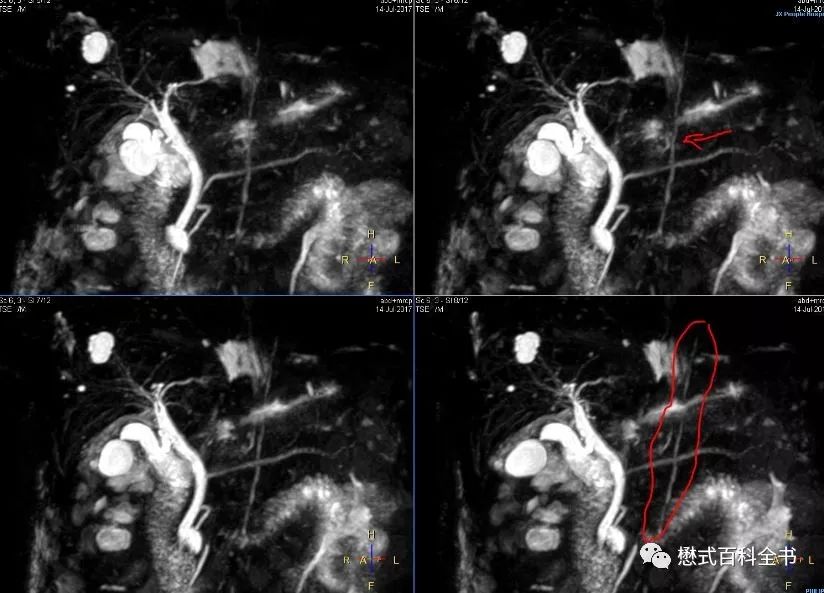

图9:MRCP注意看图中标记的线

有时候,我们组MRCP经常能看到一根比较亮的线竖着穿过胰管。有老师认为是伪影,有老师认为是其他结构。看了一些文献,有的说这个是淋巴管,扫描MRCP出现这个的概率不多。还有文献说和人种有关系,貌似中国人出现这个多。这个位置看着是胸导管?(我们专门有针对胸导管成像的序列,效果非常好)对于这个问题,我也没有过多研究,看看老师们有什么高见,可以留言。